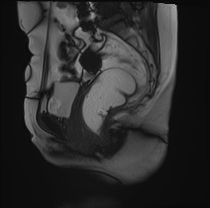

矢状位动态扫描

排便动态扫描

研究显示,患者排便时盆底整体下降异常,肛提肌裂孔异常增宽。

可见肛直肠交界处严重异常下降。

可见直肠肛门内套叠,直肠折叠入肛管。另可见少量直肠前膨出。

可见中度膀胱膨出。

可见轻度阴道脱垂。

子宫未显影——子宫切除术后状态。

患者排便时盆底整体下降异常,肛提肌裂孔异常增宽。

严重的肛门直肠交界处异常下降,伴直肠肛门套叠和轻微的前部直肠膨出。

中度膀胱膨出。

轻度阴道脱垂。